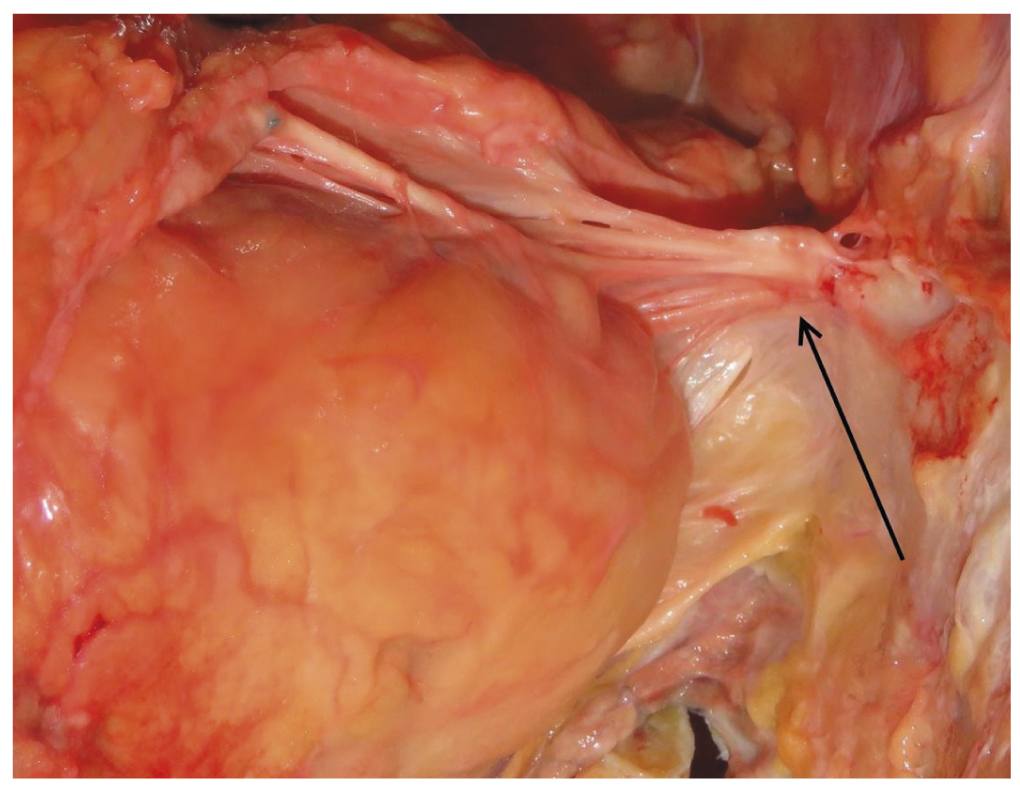

При наличии признаков бывшего оперативного вмешательства на органах грудной клетки, после отсепаровки мягких тканей груди пересекаются рёбра, начиная с третьих, до рёберных дуг; вышележащие рёбра и грудино-ключичные сочленения вначале не затрагиваются. Рёбра пересекают как можно латеральнее (на границе хрящевой и костной части). Образовавшийся частично подвижный фрагмент грудной клетки эксперт приподнимает за нижний конец грудины, при этом со стороны брюшной полости осматривает средостение и отсепаровывает клетчатку. В норме между задней поверхностью грудины и органами средостения имеется небольшое количество рыхлой жировой клетчатки, после ранее проведённых операций там могут образовываться соединительнотканные спайки. Подходя к уровню III–II рёбер, следует обращать особое внимание на наличие крупного сосуда между отделяемой передней грудной стенкой и перикардом. Внутренняя грудная артерия (почти всегда — левая), отсепарованная от грудной стенки и «ныряющая» в перикард, обычно довольно легко визуализируется таким способом (рис. 1).

Рис. 1. Маммарокоронарный шунт (стрелка).

При обнаружении такой артерии, формирующей маммарокоронарный шунт, можно наложить на неё лигатуру для удобства дальнейшего поиска и исследовать артерию «на месте», для чего потребуется пересечь грудину на уровне примерно вторых межреберий. Проксимальную часть внутренней грудной артерии следует обязательно вскрыть на всём её протяжении до подключичной артерии, так как данный сосуд, анастомозированный с венечной артерией и, соответственно, испытывающий повышенную нагрузку, может быть поражён атеросклерозом. Не следует забывать и об исследовании правой внутренней грудной артерии, так как может иметь место и бимаммарное шунтирование; кроме того, правая грудная артерия может быть изъята в качестве кондуита.